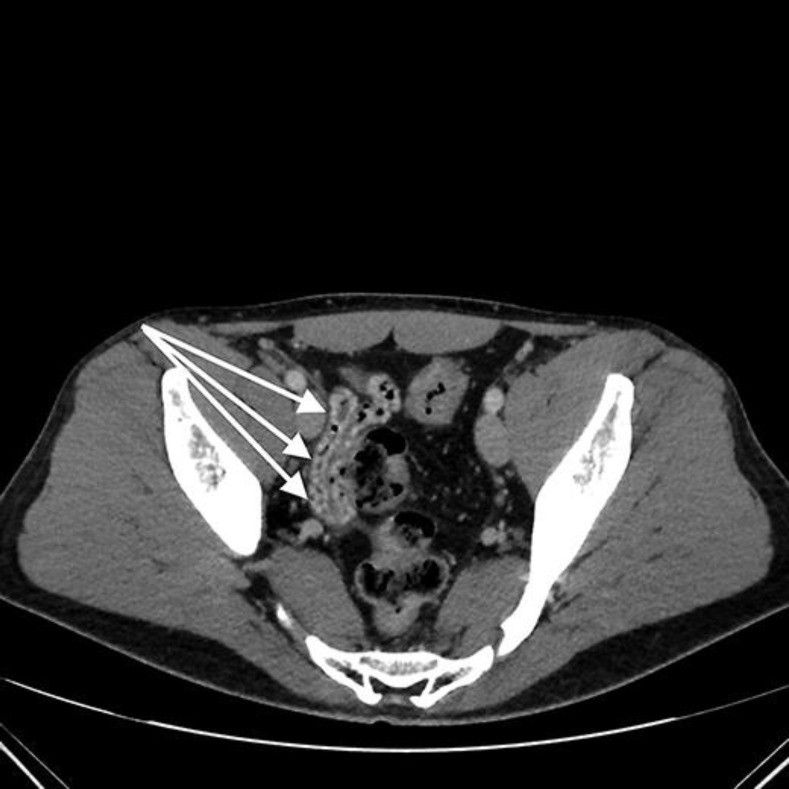

Гастродуоденоскопия с максимальным осмотром двенадцатиперстной кишки ничего не выявила. При компьютерной томографии с болюсным усилением признаков портальной гипертензиии и тромбозов в селезеночной вене не обнаружено, но были очевидны варикозные изменения в ветвях верхней брыжеечной вены в левой эпи- и мезогастральной областях. Обнаружены также признаки варикозного расширения вен в стенке тощей кишки (рис. 1), подвздошной кишке (рис. 2) и ободочной кишке (рис. 3).

Рисунок 1 [1].